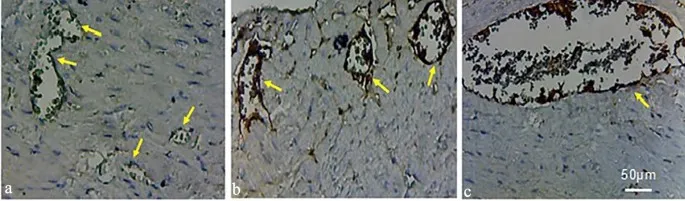

Впоследствии крысы были ethically sacrificed для facilitate удаления сердца, followed by иммуногистохимическим окрашиванием на глиальный фибриллярный кислый белок (GFAP - Glial Fibrillary Acidic Protein).

• Нейровоспаление